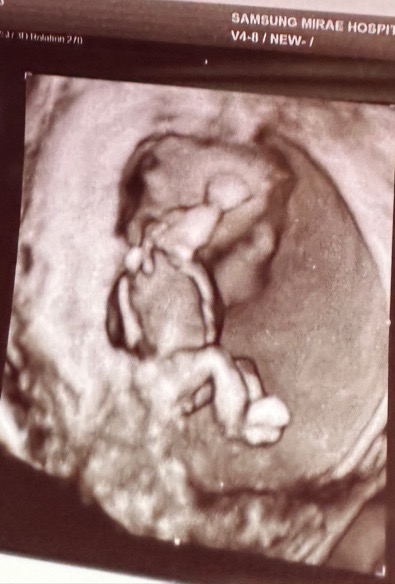

혹시 이거 꼬추인가요??

아기 다리사이에 뿅 튀어나온거 혹시 꼬추일까요??

저 사진은 12주4일이요!

고추같아보여요,,,